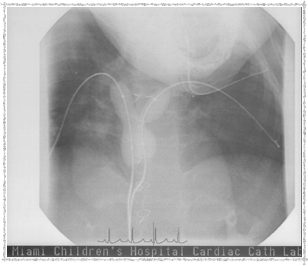

In 2003, Elyse underwent a catheterization procedure at Miami Children's Hospital, performed by Dr. Evan Zahn. Below are some pictures that Dr. Zahn provided. She left the hospital the same day — remarkable!

Catheterization 2003 - Before

Before the procedure